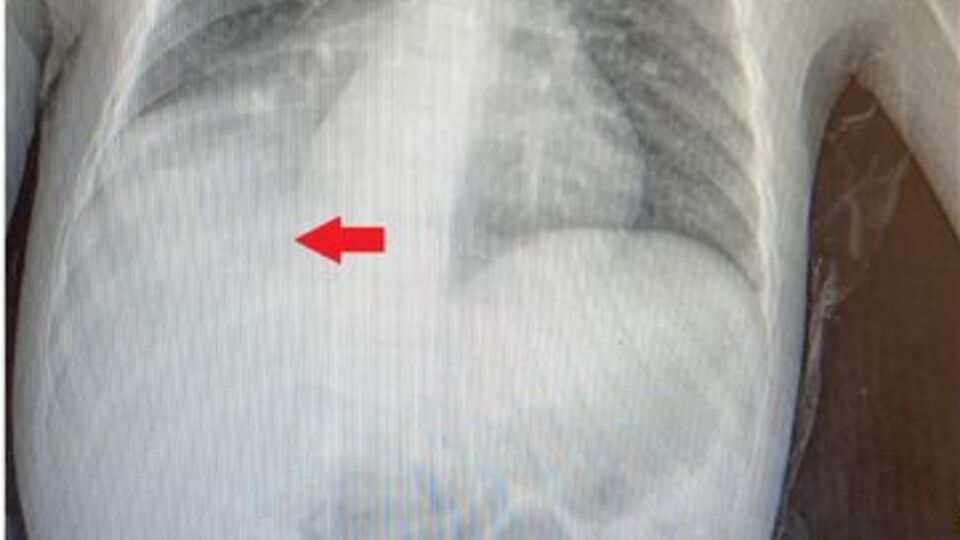

Başakşehir Çam ve Sakura Şehir Hastanesi Çocuk Cerrahi Kliniği’nden Opr. Dr. Mehmet Çakmak, "Acil servisteki doktor arkadaşlarımızın muayenesi sonrası çekilen akciğer röntgeninde, sağ alt bölgede sıvı birikimi nedeniyle bize danıştılar. Hastanın öyküsünü annesinden tekrar dinlediğimizde, şikayetlerinin 1 yaşında kardeşleriyle otururken karpuz çekirdeğini ağzına götürmesi sonrası başladığını öğrendik. O zaman çekilen akciğer röntgeninde herhangi bir patolojik bulguya rastlanmayınca, 3 yıl boyunca semptomlarının ara ara iyileşmesi nedeniyle de daha çok astım, bronşit pnömoni gibi teşhisler düşünülmüş ve buna yönelik tedaviler verilmiş. Çünkü normalde yabancı cisim aspirasyonlarında, semptomlar gerilemez. Biz, annesinin verdiği öyküyü dinleyince tomografi çektik ve sağ akciğer alt bölgeyi havalandıran bronşun, bir yabancı cisimle tıkalı olduğunu tespit ettik. Yaptığımız bronkoskopide bir karpuz çekirdeğine rastladık ve işlem esnasında karpuz çekirdeğini çıkardık" dedi.